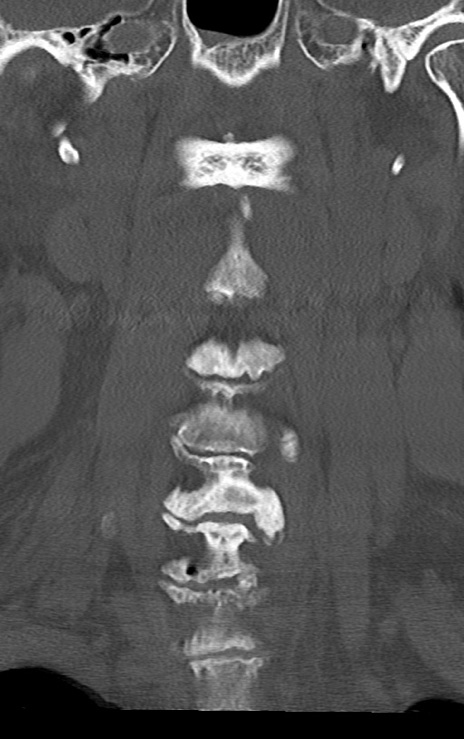

頚椎CT

矢状断像